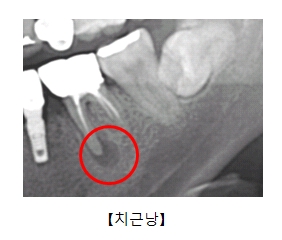

치근낭(Radicular cyst)

증상

치근단 부위 부종

,

치아 흔들림

관련질환

근단 주위 농양

진료과

치과